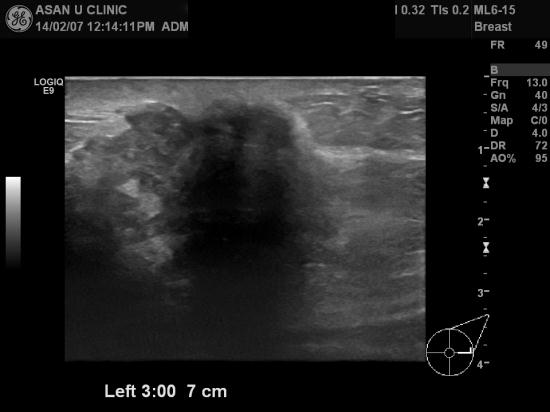

좌측유방에 만져지는 몽우리 주소로 내원하여

본원에 조직검사 의뢰되신 48세 여성분입니다.

조직검사상 좌측 유방의 두군데에 침윤성 유방암으로 진단되었으며

현재 겨드랑이에도 암전이 의심되는 림프절들의 비대가 있어

매우 진행된 상태로 여겨집니다.